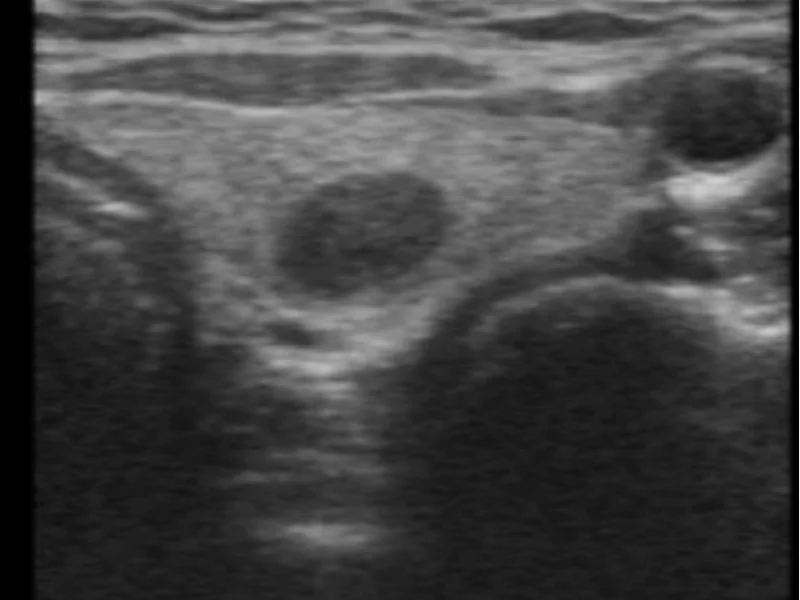

Múltiplos nódulos (bócio multinodular)

Não é necessário puncionar todos!

Escolher para puncionar:

- Nódulo mais suspeito (TR4 ou TR5)

- Nódulo dominante (maior)

- Se todos benignos: puncionar 1-2 maiores

Motivo: Risco de câncer é similar em nódulo único vs múltiplos nódulos.